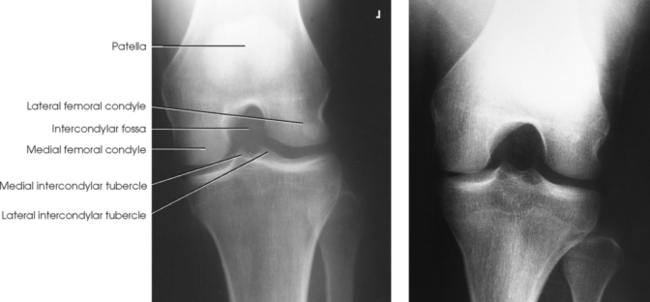

Structures shown: The image shows the intercondylar fossa of the femur and the medial and lateral intercondylar tubercles of the intercondylar eminence in profile (Fig. 6-139). Holmblad1 stated that the degree of flexion used in this position widens the joint space between the femur and tibia and gives an improved image of the joint and the surfaces of the tibia and femur.

Structures shown: This axial image shows an unobstructed projection of the intercondyloid fossa and the medial and lateral intercondylar tubercles of the intercondylar eminence (Figs. 6-142 and 6-143).

Fig. 6-142 Camp-Coventry method. A, Flexion of knee at 40 degrees. B, Flexion of knee at 40 degrees in a 13-year-old patient. Note epiphyses (arrows).

Fig. 6-143 Flexion of knee at 50 degrees (same patient as in Fig. 6-142): Camp-Coventry method.